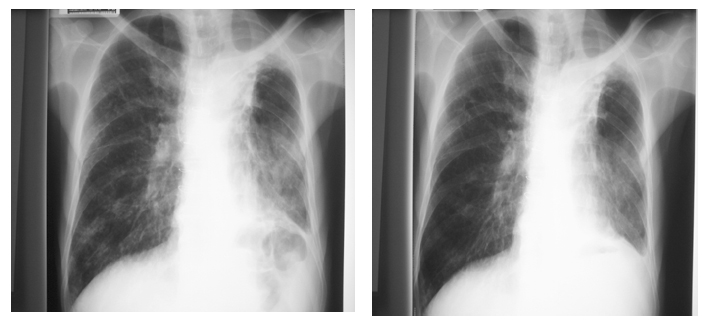

He was transferred to our hospital on 22/8/2005.Two days after completing the course of antibiotic, patient developed fever and increased purulent sputum again. He had no choking history and did not have abdominal pain, dysuria or arthralgia that suggestive of other sources of infection. He had no pet at home and no recent travel history. Reviewing his medication, he was taken Pyridostigmine bromide 20mg b.d., Lansoprazole 30mg daily, Senokot tab 15mg nocte and Combivent inhaler puff 2 q.i.d., Beclomethazone (250 mcg/dose) puff 2 q.i.d and Erythromycin 500mg b.d.. On physical examination, he had temperature of 38o C and crepitations over right lower zone of chest. He showed no dysphonia or fatiguability and no ptosis or diplopia. His power was full and no focal neurological sign demonstrated. The examination of cardiovascular and abdomen system were unremarkable. His CXR showed new right lung patchy infiltrates (Fig. 1)

His white cell count was 14.3×109 /L with 14.3% neutrophils and 32.3% lymphocytes. His hemoglobin level was 12.4g/dL. He had normal renal function and normal liver function except mildly elevated ALP of 184 U/L. HBsAg and HCV Ab were negative. His globulin level was 32 g/L. Fasting glucose was 4.5mmol/L. Repeated sputum culture grew Pseudomonas aeruginosa and was resistant to ciprofloxacin. Mid-stream urine and blood culture were negative. Fever was down and clinical and radiological (Fig.2) improved with Timentin and Gentamycin. However, patient developed recurrent episodes of fever and purulent sputum once antibiotics stopped. (Fig.3)